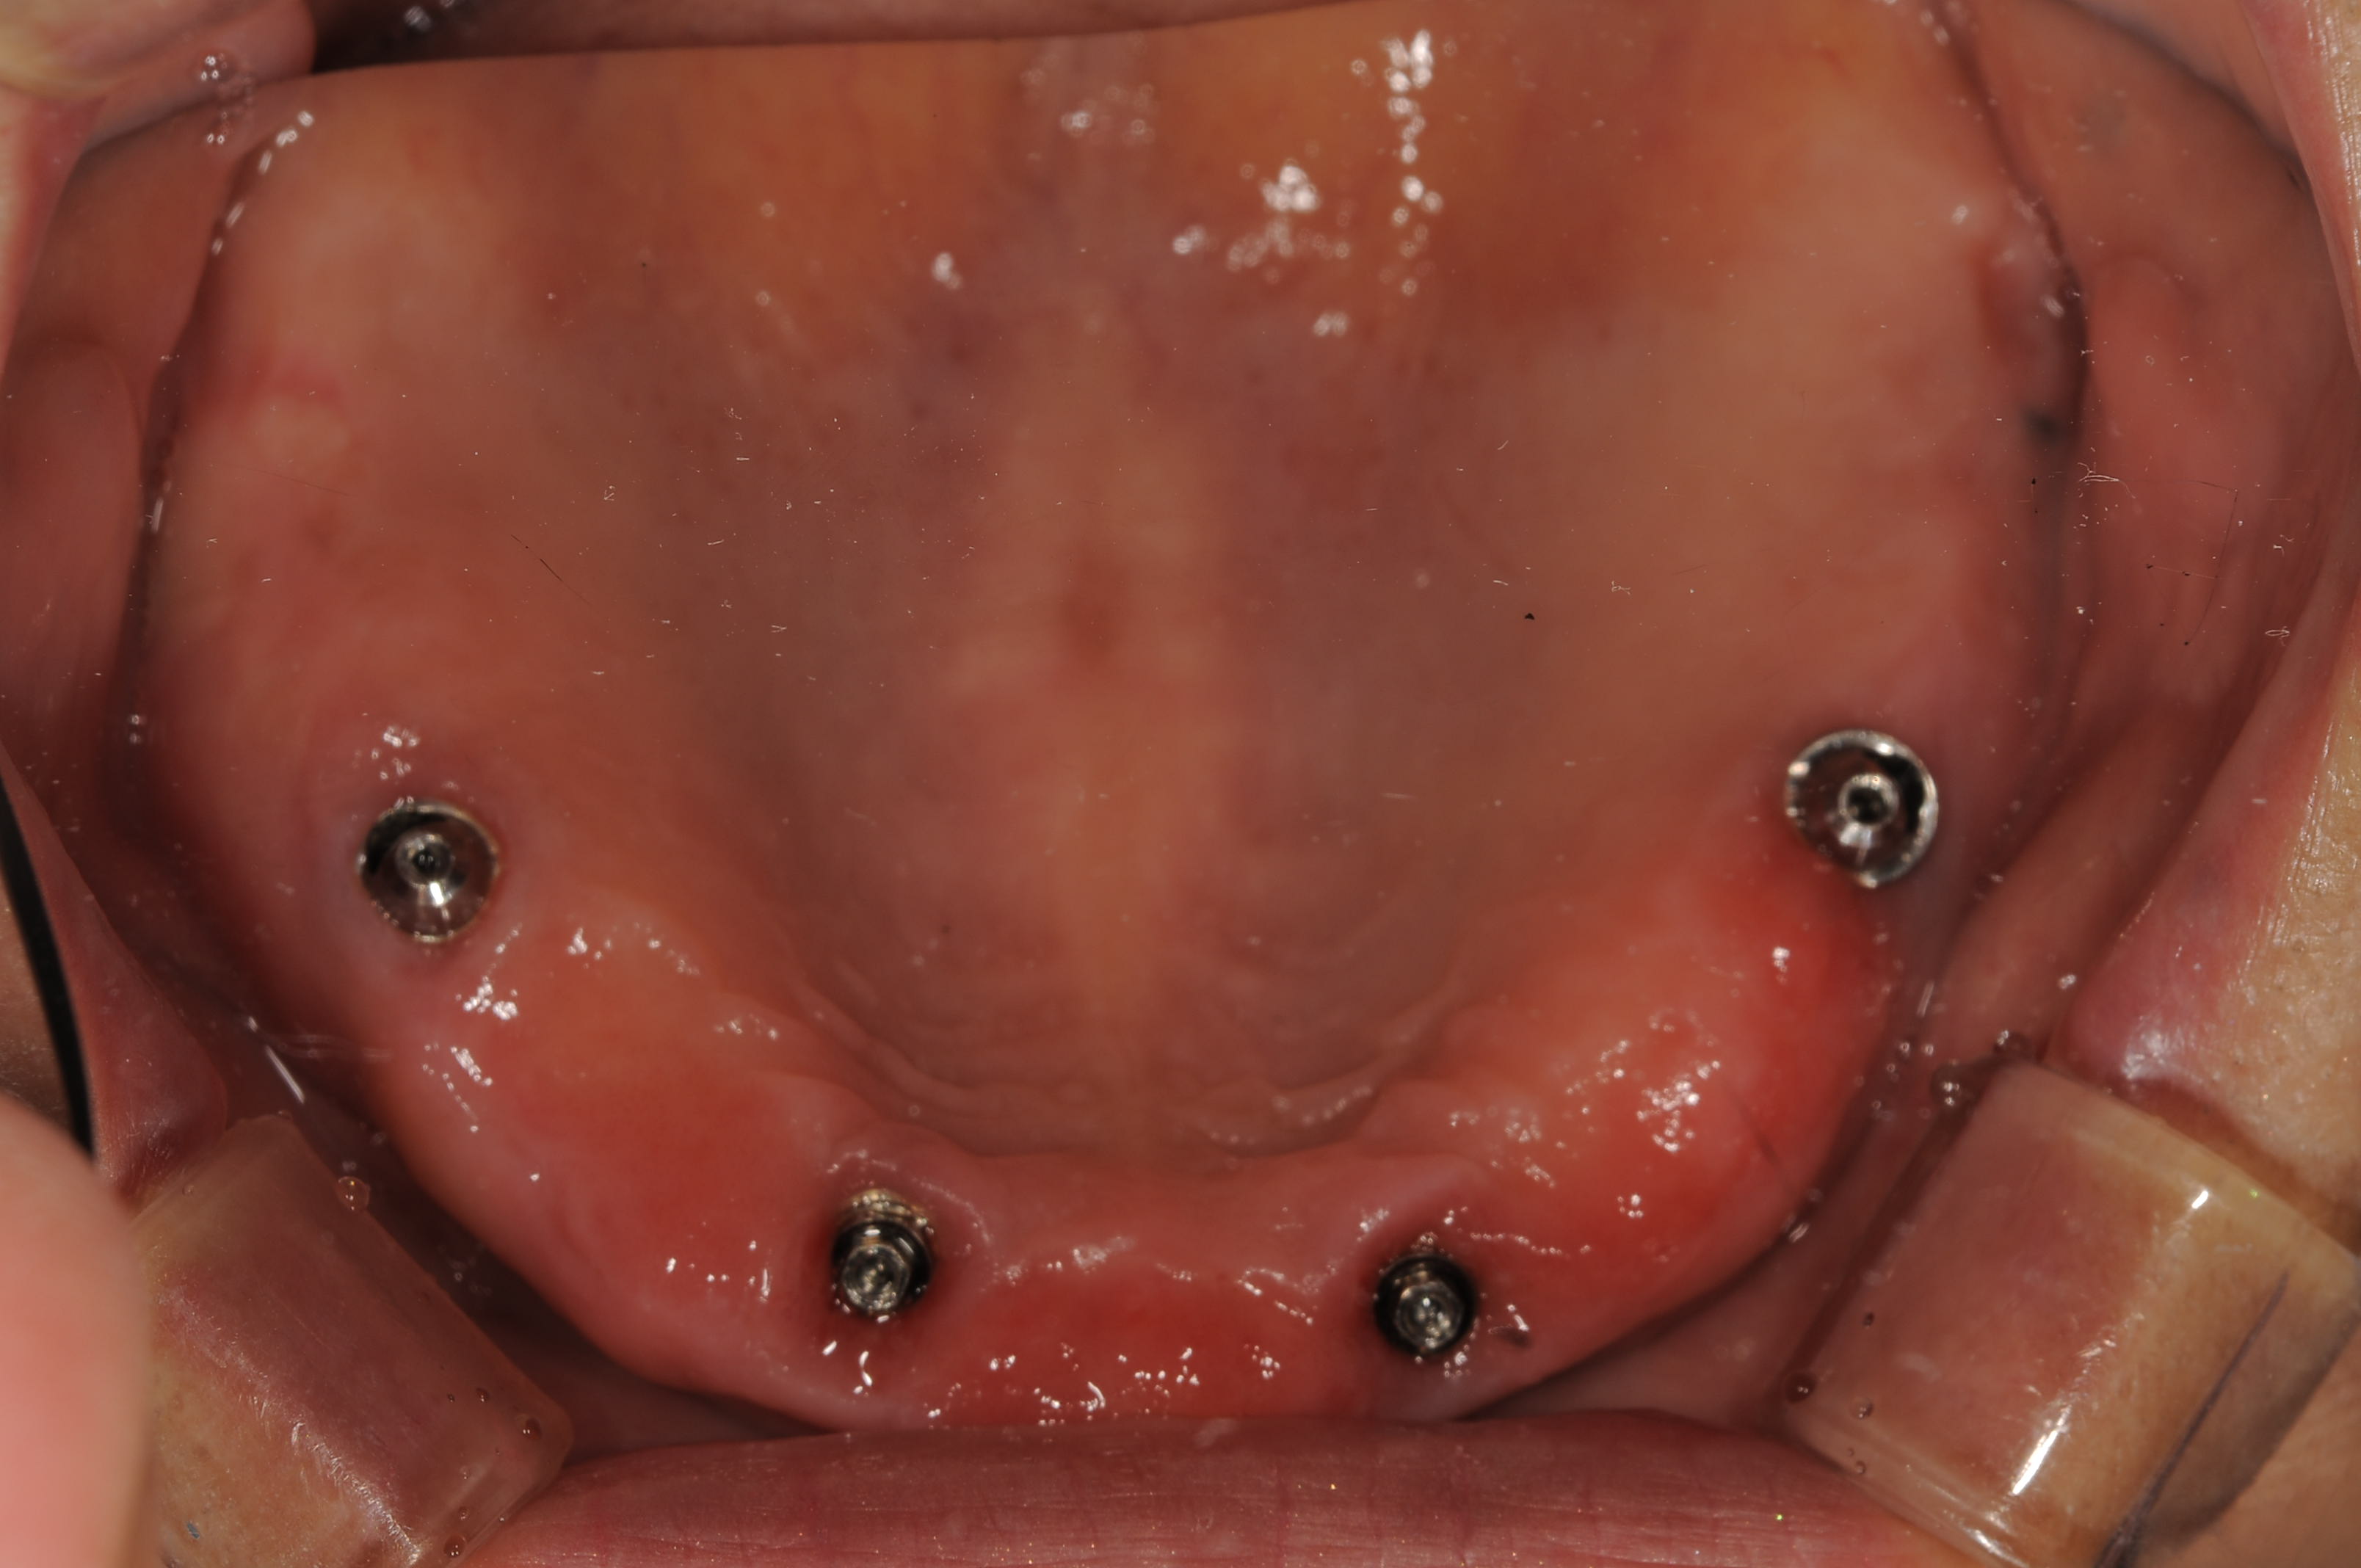

最終補綴物装着時のインプラントの埋入ポジション